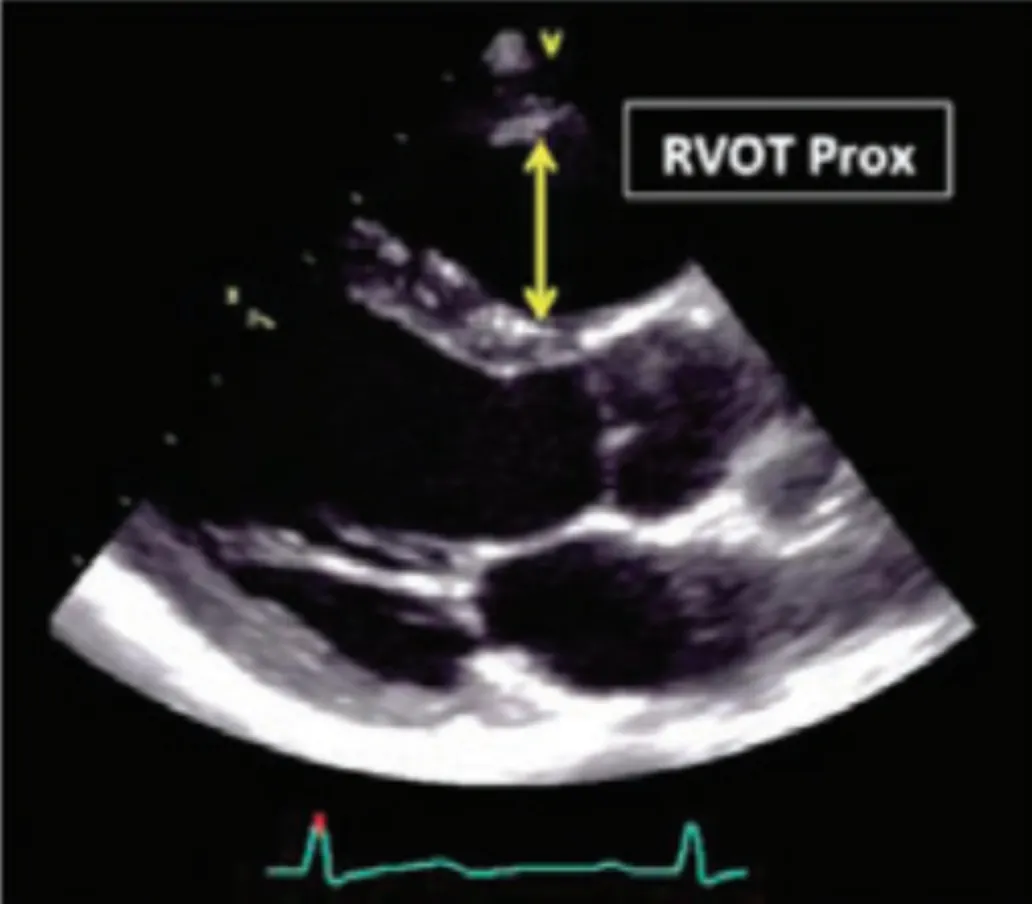

RV outflow view

Normal RV outflow tract diameter : 1.8~3.4 cm

Pulmonary arterial end-diastolic pressure (PEDP) = 4(Ved)^2 + RAP

Mean pulmonary artery pr = 4 (PRVBD)^2 + RAP